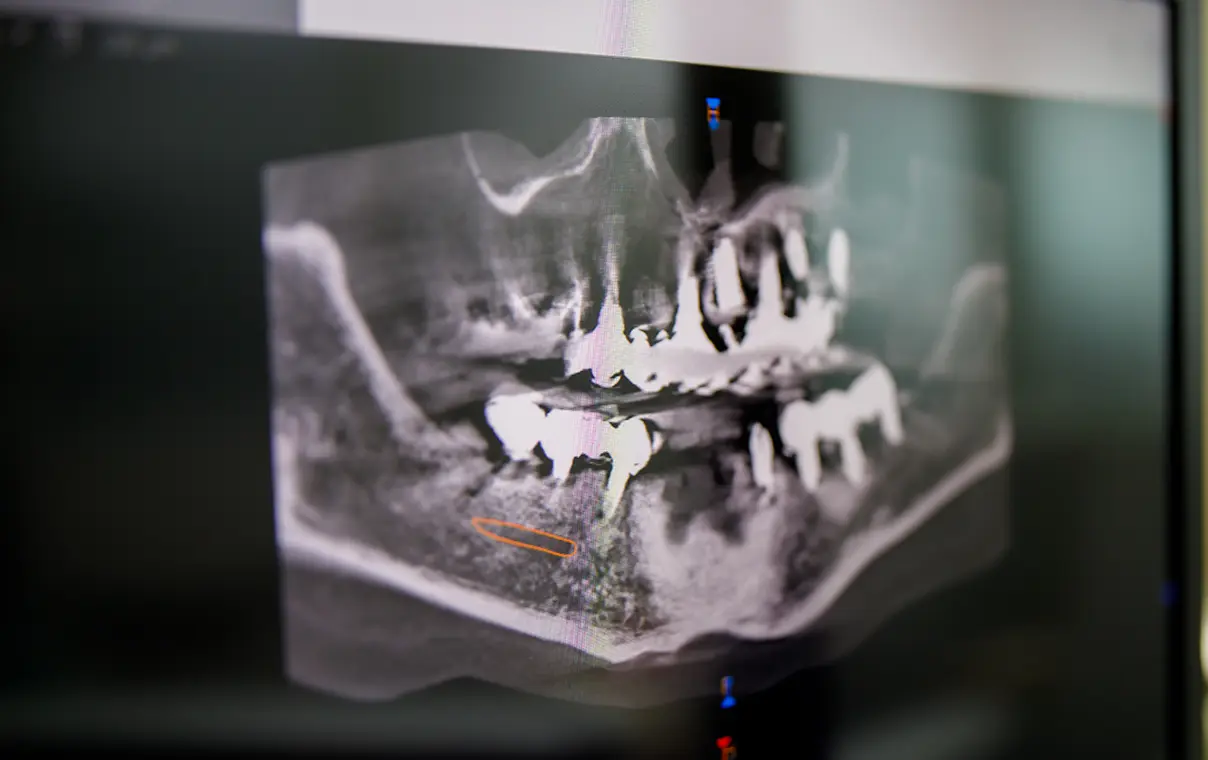

診療内容に関係なく、検査の際は歯科用CTで撮影して、より精密な3Dデータをもとに診療いたします。歯科用CT撮影は自費診療で行なう検査ですが、患者様により適切な治療を提供するために無料で実施しています。

虫歯や歯周病、インプラント、矯正など病気や治療法への不安や疑問はお気軽にご相談ください。検査結果をもとに、患者様の歯の状態と合わせてお答えします。また、ご希望の方にパノラマレントゲン写真をプレゼントしています。